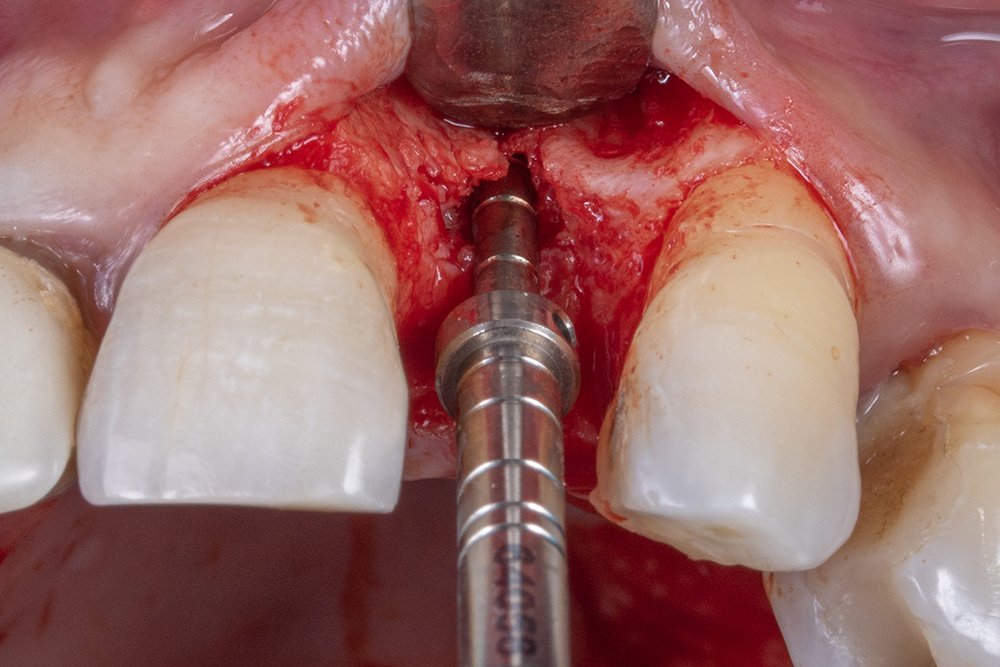

Após realizar a perfuração óssea, utilizou-se o túnel check para mensurar as perfurações e o paralelismo na hora de instalar os implantes.

O implante escolhido foi Cone Morse da Implacil De Bortoli, pois possui certas vantagens comparados aos outros sistemas, como ótimos resultados em relação a manutenção e excelente distribuição de forças fisiológicas ao redor dos tecidos peri-implantares, e mínimo deslocamento do pilar.

Ao final da instalação do implante, é importante mensurar a distância do implante intraósseo, devendo ficar de 2 a 3 mm, considerando a mucosa peri-implantar.